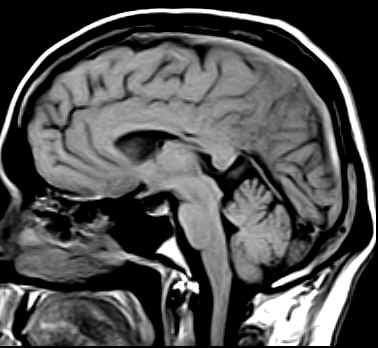

Diffuse hypointense areas on the T1W images which turn hyperintense on the Proton & T2W images are noted in the left parietal lobe. An area which is predominantly hypointense with a hyperintense rim on all sequences is noted in this lesion (subacute blood). The lumen of the superior sagittal sinus shows a hyperintense signal (no flow on the MRV-images not available) representative of a thrombus in this case.

·                     May find a lack of the normal flow void within a dural venous sinus (e.g. in the superior sagittal sinus).

·                     May see intense tentorial enhancement (collateral's/venous stasis).